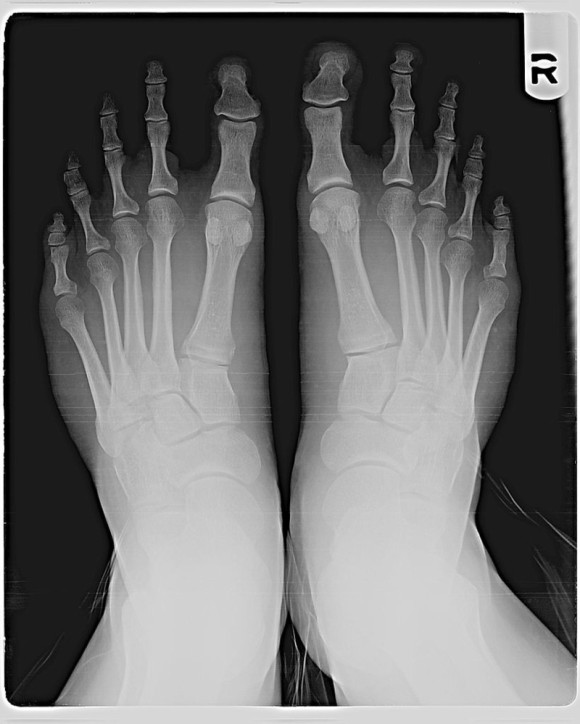

モートンの爪先のレントゲン写真